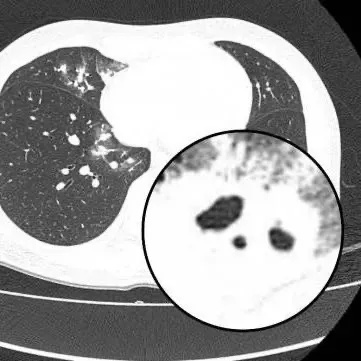

胸部CT显示其双肺多发感染

伴多发空洞形成

医生查房时,捕捉到CT上形似“鬼脸”的特殊影像(即“鬼脸征”),并伴有“晕轮征”,高度怀疑隐球菌肺炎。医生追问夏女士近期是否曾接触鸟类、禽类及饲养宠物,夏女士否认。

在影像学表现方面,典型CT表现是单发/多发结节伴“晕轮征”,结节液化坏死可形成空洞形似“鬼脸征”,空洞常为薄壁空洞、无液平。